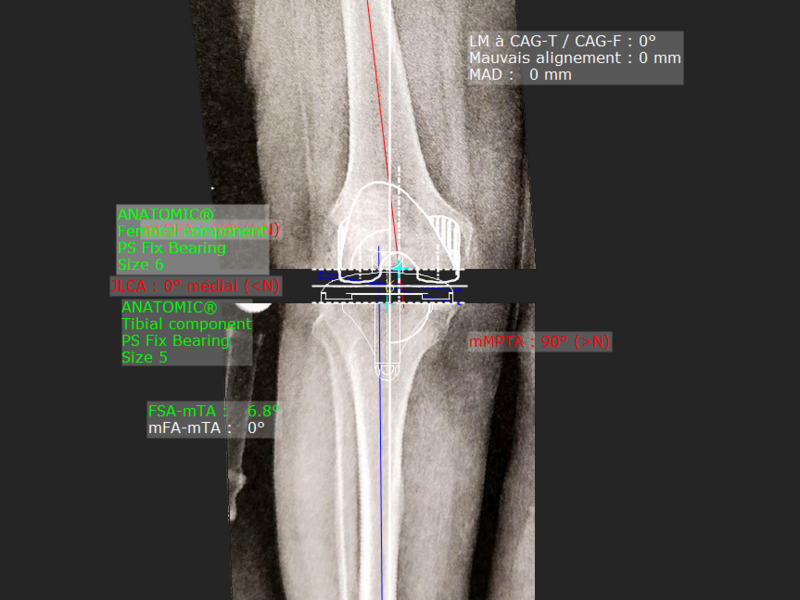

Album photo